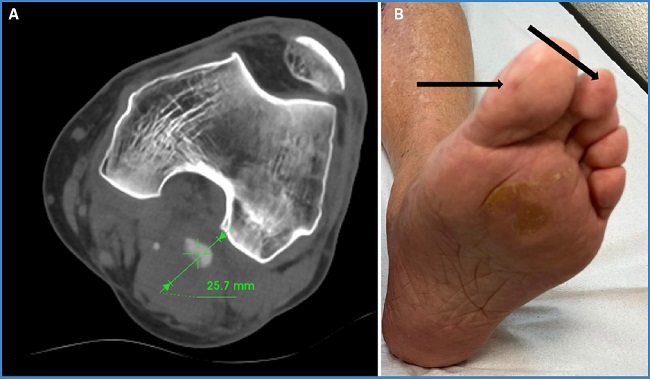

Presentamos el caso de un paciente masculino de 65 años, exfumador y sin otros factores de riesgo cardiovascular, que acudió por sospecha de trombosis venosa profunda (TVP). Como hallazgo incidental se detectó un aneurisma que afectaba a la primera y a la segunda porción de la arteria poplítea (P1-P2) en el miembro inferior izquierdo (MII), con un diámetro de 25 mm en el eco Doppler. En la exploración física presentaba pulsos distales asociados a un importante edema en MII y masa pulsátil en el hueco poplíteo. Se completó estudio con angio TC y se descartaron dilataciones aneurismáticas en otras localizaciones (Fig. 1A).

Figura 1. A. Aneurisma poplíteo izquierdo, diámetro al diagnóstico. B. Flechas negras: lesiones cianóticas puntiformes digitales sugerentes de embolización distal.

Se dio de alta con tratamiento anticoagulante, a la espera de cirugía diferida; sin embargo, 48 horas después de recibir el alta acudió nuevamente a Urgencias con dolor torácico irradiado a los miembros superiores y fiebre (38 °C). Presentaba lesiones purpúricas puntiformes de nueva aparición en los dedos de los pies del MII, indicativas de embolización distal (Fig. 1B).